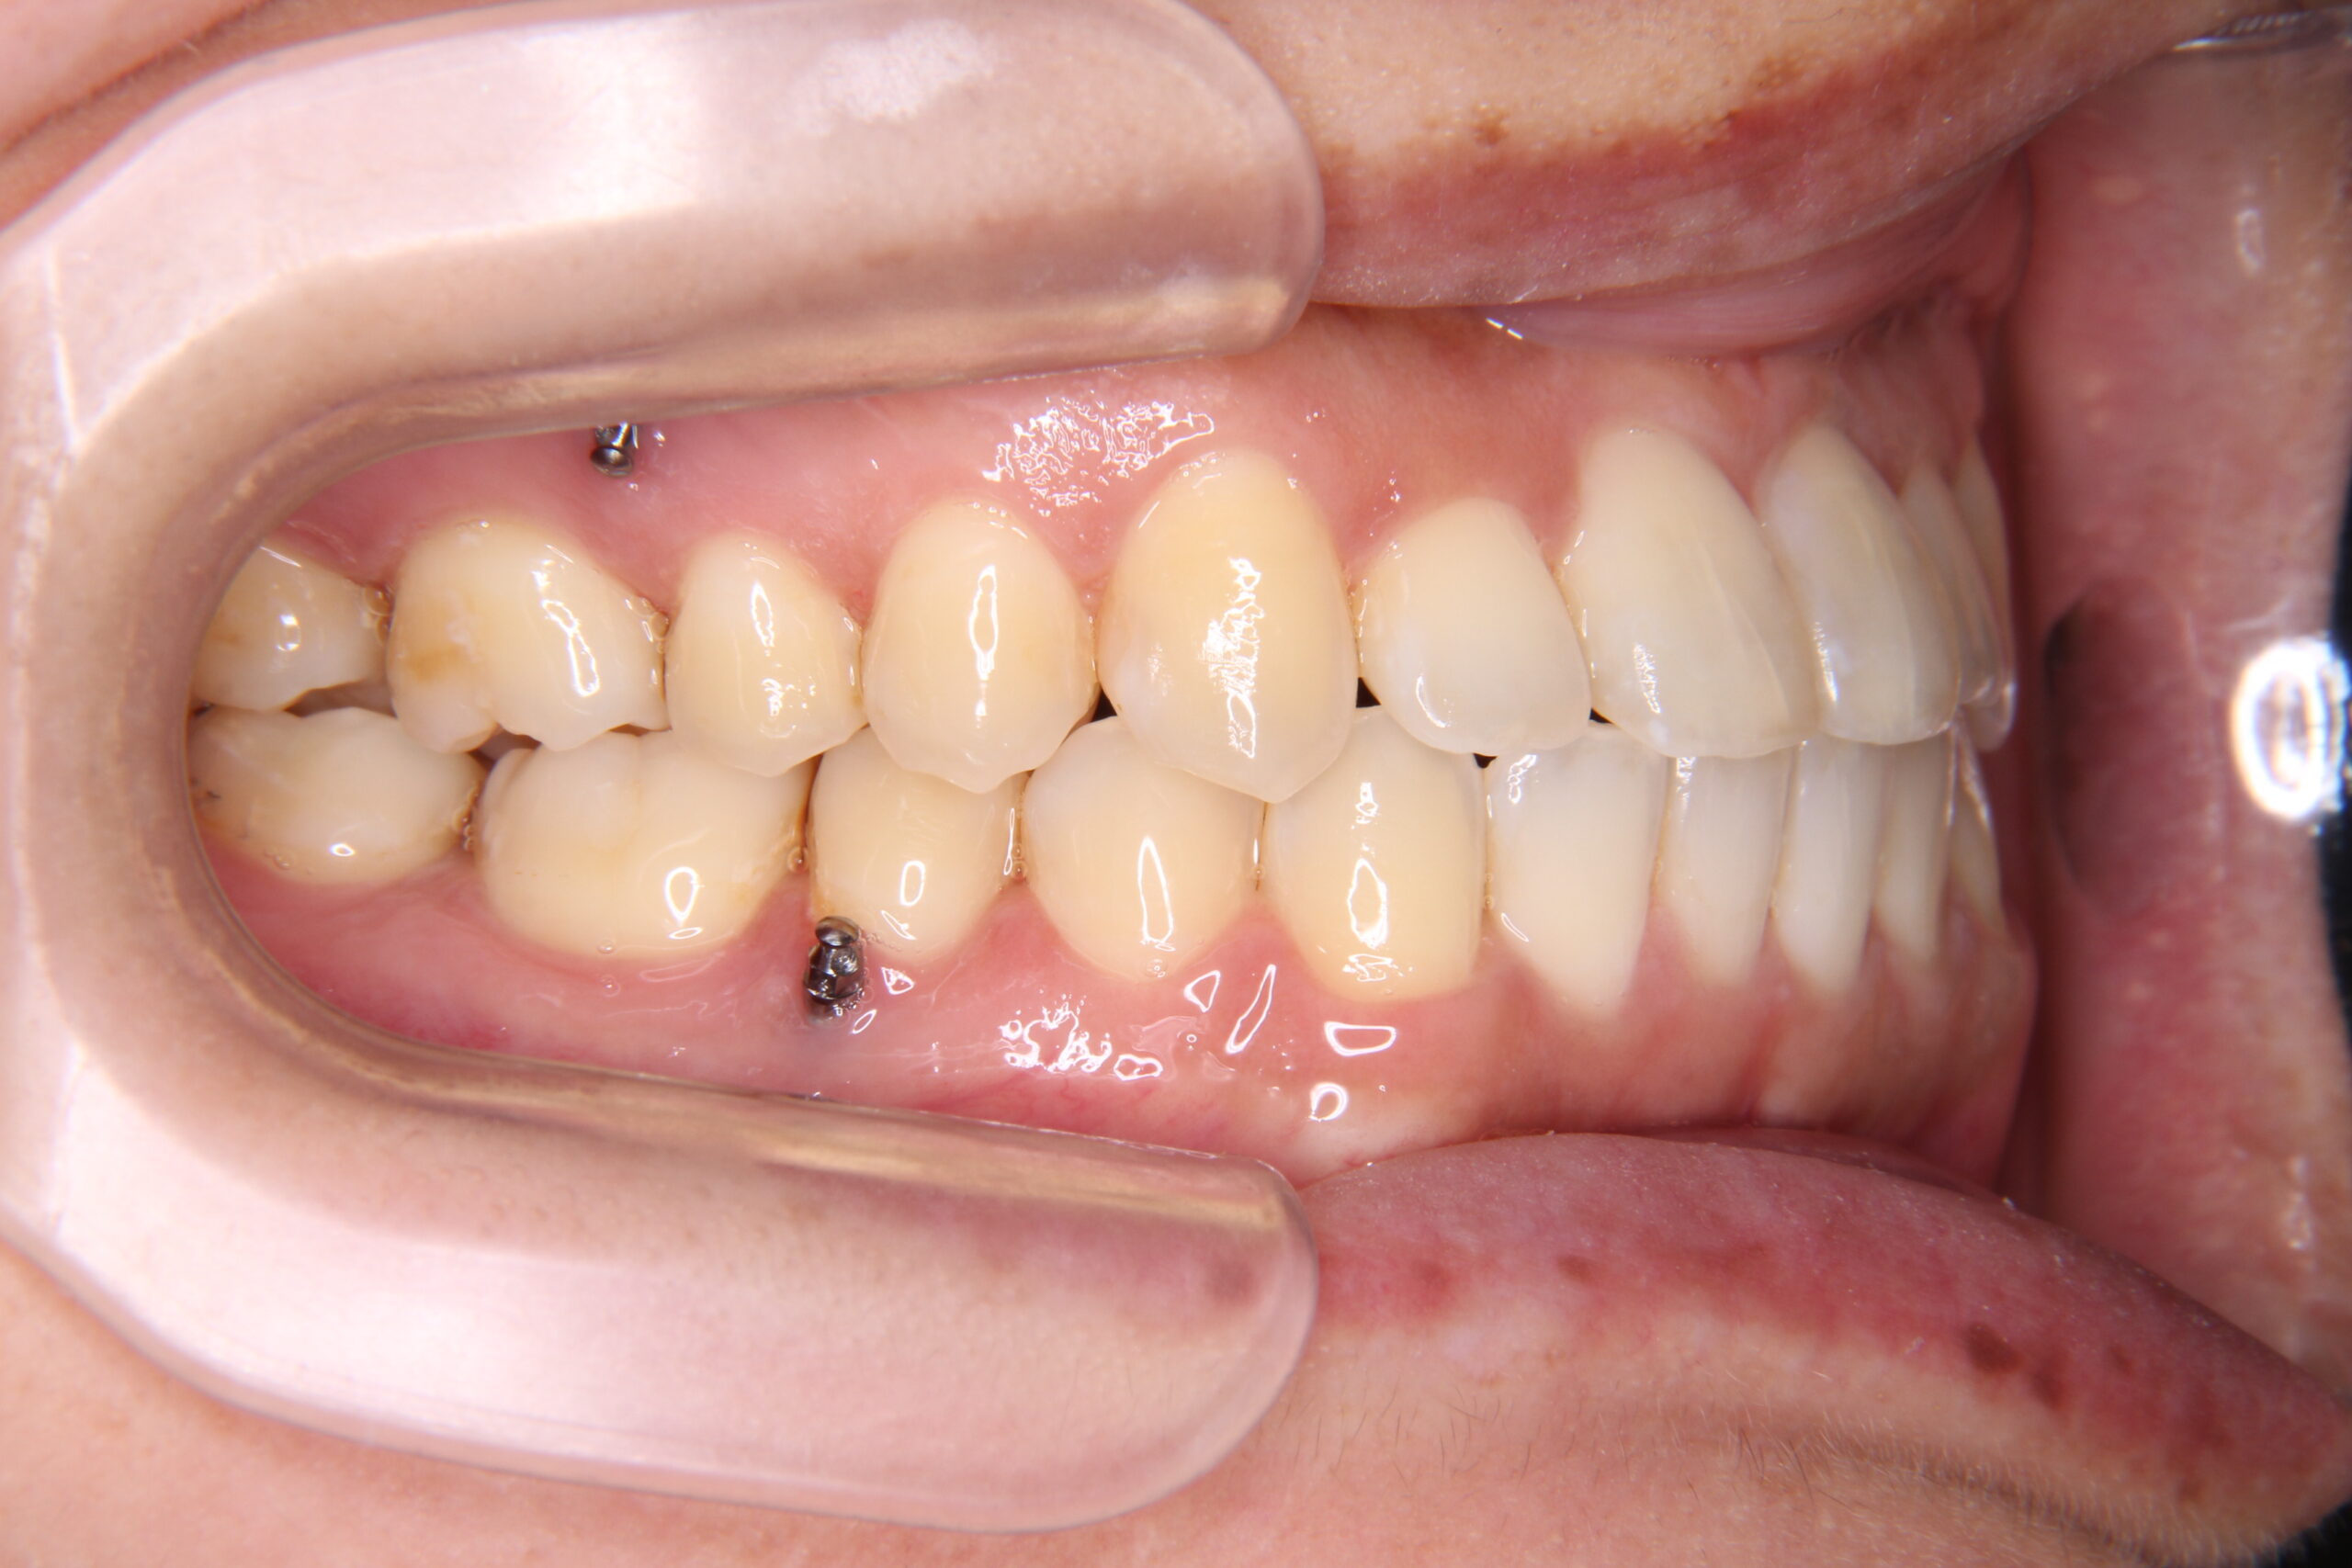

マウスピース矯正やワイヤー矯正に加え、必要に応じてアンカースクリューを活用することで、より複雑で難しい歯並びの症例にも対応しています。これにより、従来の矯正だけでは難しかった歯の移動も可能となり、幅広い治療の選択肢をご提供できます。

症例

矯正歯科専門の歯科医師が専門的な知識と確かな実績を

もとに患者様にあった最適な治療プランをご提案します。